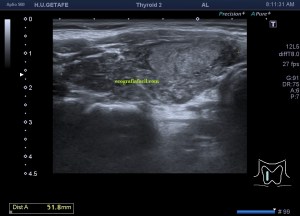

250. Ecografía de Tórax, Líneas A y B.

Llevaba tanto tiempo queriendo explicar esto…Hoy voy a tratar de explicarte de forma muy sencilla y sin meterme en muchos jardines, cómo debes ver un patrón aéreo normal en una exploración de tórax o en aquellas exploraciones donde el pulmón pueda ser valorado, por ejemplo en la ecografía de mama.

Si el pulmón está aireado y sano vamos a ver esta imagen:

1. Líneas A

Líneas A. En la imagen 1 puedes ver la normalidad de un pulmón bien aireado en esa región explorada. La anatomía radiológica, la imagen hiperecogénica que asociamos a la pleura y los artefactos en espejo de las tres líneas A paralelas a la línea que hemos denominado «Pleura» y que tan solo es la primera de las líneas especulares, es decir, artefacto de espejo que se produce entre la pared torácica y el aire del pulmón.

En conclusión, la líneas A son de NORMALIDAD. Son hiperecogénicas, lineales, paralelas  horizontalmente y equidistantes.